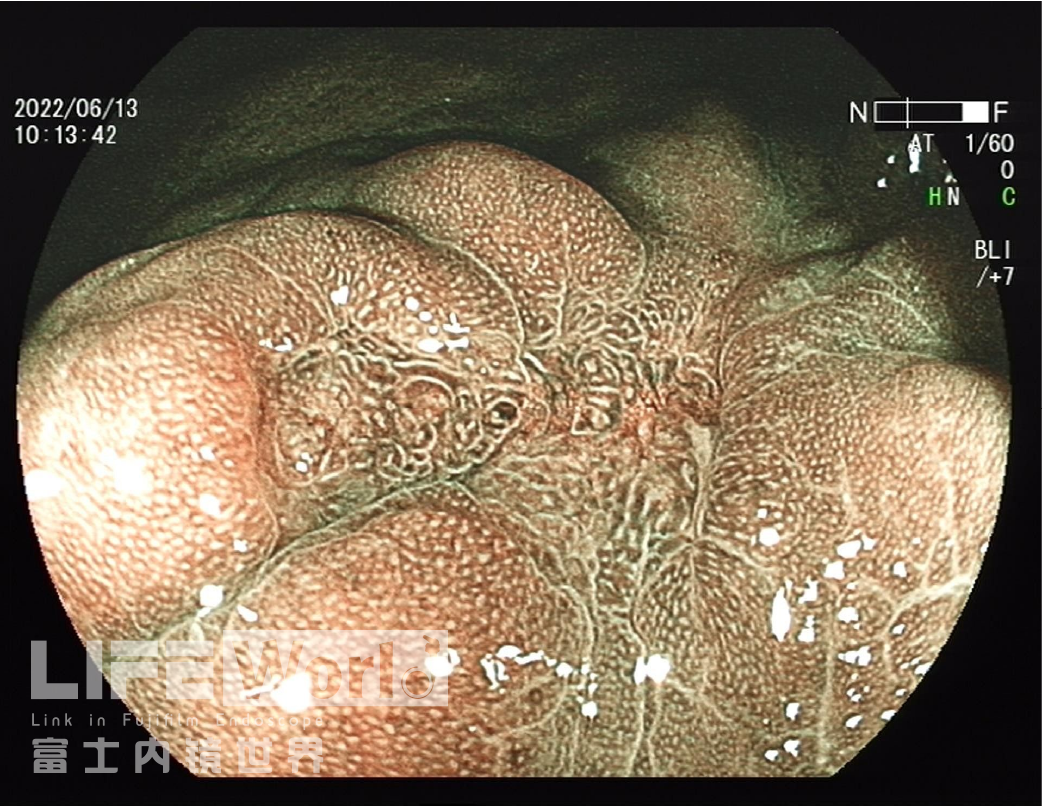

BLI模式低倍放大观察,可清晰的勾勒出病变的范围,病变的口侧端表面微结构的异型性明显,考虑为癌灶,病变的肛侧端异型性不明显,考虑为上皮内瘤变。

对考虑为癌灶的区域进行中倍放大观察:IMSP(+), IMVP(+)。

对考虑为癌灶的区域进行高倍放大观察,根据下面的胃癌放大内镜诊断流程图来进行判断。